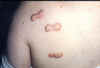

Queloides en el hombro

Cicatriz queloide en la espalda de un joven de 22 años, producido tras la exéresis de un nevus.